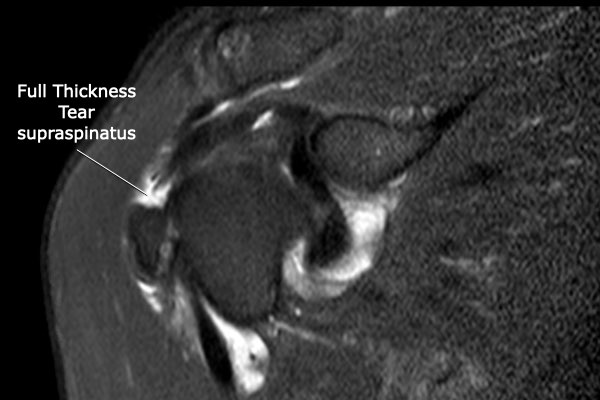

Rách toàn bộ chiều dày hoàn toàn

Nhấp vào hình ảnh để phóng to, sau đó cuộn qua các lát cắt.

Có hình ảnh rách toàn bộ chiều dày gân cơ trên gai kèm co rút và teo cơ.

Lưu ý các dải mỡ trong cơ tròn bé, cơ trên gai và cơ dưới gai.

Các vị trí rách toàn bộ chiều dày thường gặp nhất bao gồm:

- Cơ trên gai (Supraspinatus)

Rách phần trước xa của gân cơ trên gai là vị trí thường gặp nhất.